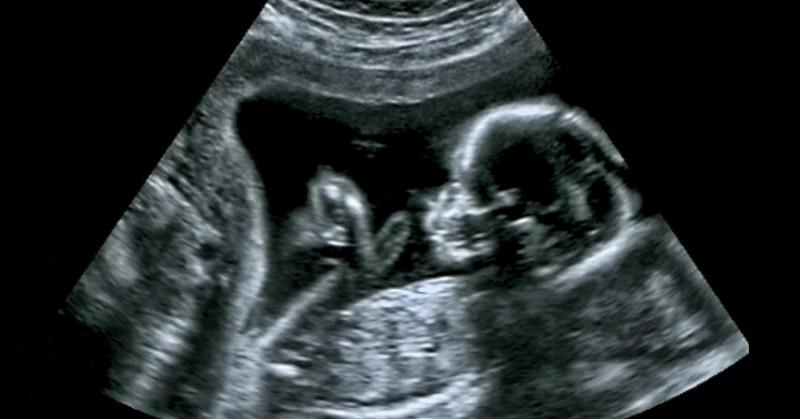

Pesquisas recentes indicam que o autismo pode ter parte de sua origem ainda no útero materno — e que as bactérias intestinais da gestante desempenham um papel mais importante do que se imaginava.

A microbiota é um conjunto de trilhões de microrganismos que habitam o intestino e regulam processos como metabolismo, imunidade e produção hormonal. Durante a gestação, esse equilíbrio pode mudar naturalmente, influenciando sinais químicos que atravessam a placenta e chegam ao cérebro em formação do bebê.

Pesquisadores acreditam que esse diálogo entre intestino e cérebro fetal pode ter papel decisivo no neurodesenvolvimento.

A pesquisa reforça que o ambiente dentro do útero vai muito além de nutrientes e hormônios. Sinais vindos da microbiota materna podem influenciar os circuitos cerebrais do feto em desenvolvimento.